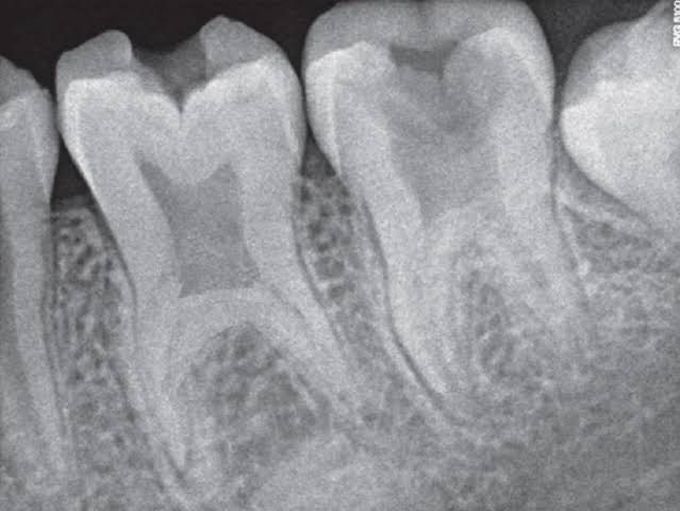

Taurodontism

Taurodontism is a developmental disturbance of a tooth in which body is enlarged at the expense of the roots. An enlarged pulp chamber, apical displacement of the pulpal floor and lack of constriction at the cementoenamel junction are the characteristic features. It appears most frequently as an isolated anomaly.